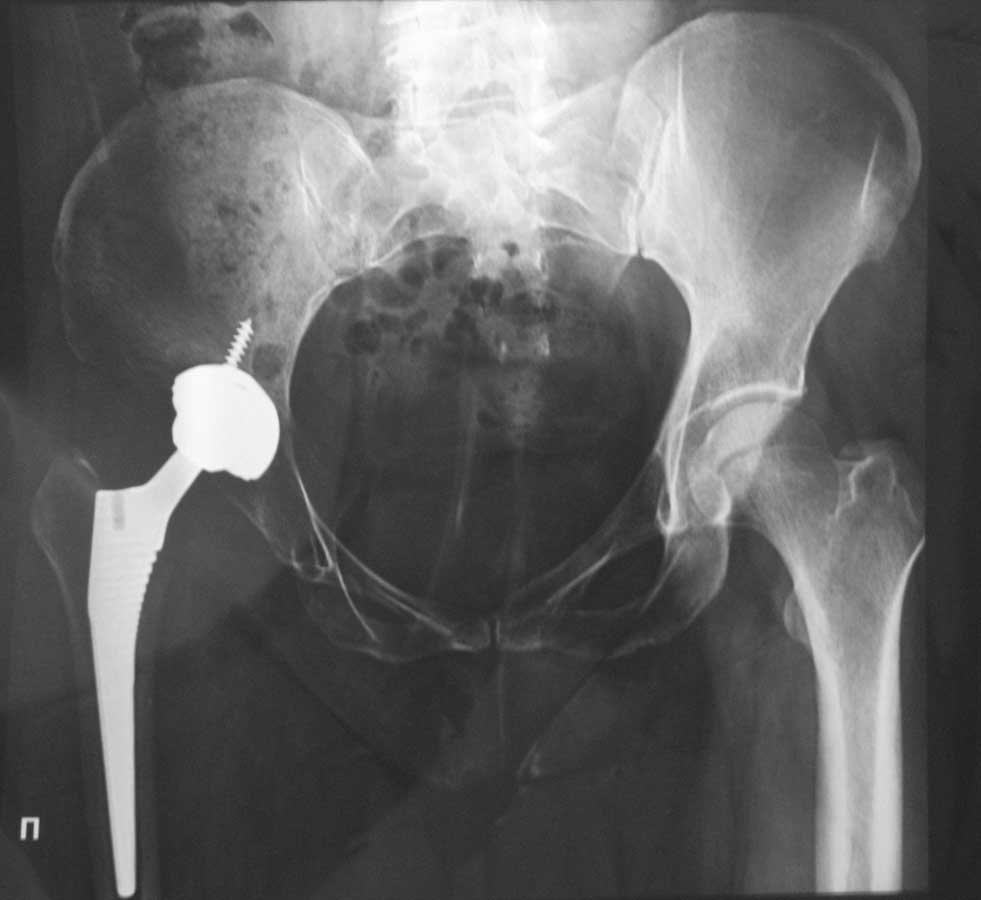

У пациентки имел место диспластичсекий коксартроз- это видно по тому, куда Вы установили чашку эндопротеза- выше истинной вертлужной впадины! По причине того, что деформация у пациентки давняя-длительное время бедро было приведено и ротировано наружу! Соответственно и коленный сустав был адаптирован к имевшей место дисфункции тазобедренного сустава! После решения вопроса с тазобедренным суставом, не произошла обратная адаптация коленного сустава, наоборот усилился вальгус в коленном суставе, имевший место и ранее, до Вашей операции!Судя по снимку, офсет у бедренной ножки стандартный! У данного типа ножек меньшего офсета небывает, есть только больший офсет! Можно конечно было использовать ножку с модульной шейкой, где можно регулировать шеечно-диафизарный угол! Но это уже невозможно-операция выполнена! Нужны снимки всей конечности и возможно коррегирующей остеотомией области коленного сустава можно будет решить возникшую проблему, при отсутствии нестабильности медиальногосвязочного комплекса коленного сустава !

боль в коленном суставе может быть вызвана хорошо фиксированной бц ножкой. Но здесь похоже проблемы в другой плоскости-высокий центр ротации вмегда ввзывает проблемы, в данном случае прогрессирование вальгуса (исходный офсет был наверное меньше). Остеотомии на бедре не восстановят биомеханики тб, рискуете получить еще больше непонятных проблем, в том числе при ревизии. В 42 года нужно перебивать чашку или весь имплант(вероятнее) а потом спокойно заниматься коленом.